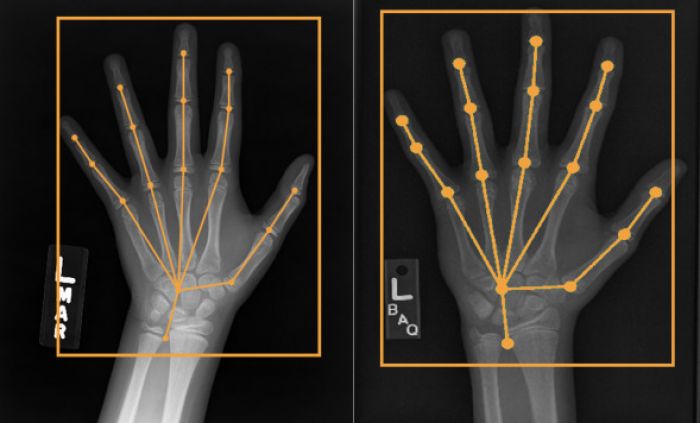

HAND POSE ESTIMATION FOR PEDIATRIC BONE AGE ASSESSMENT

Method